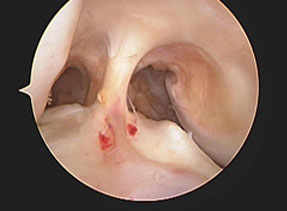

前十字・後十字靭帯断裂。十字靭帯が2本とも消失している。